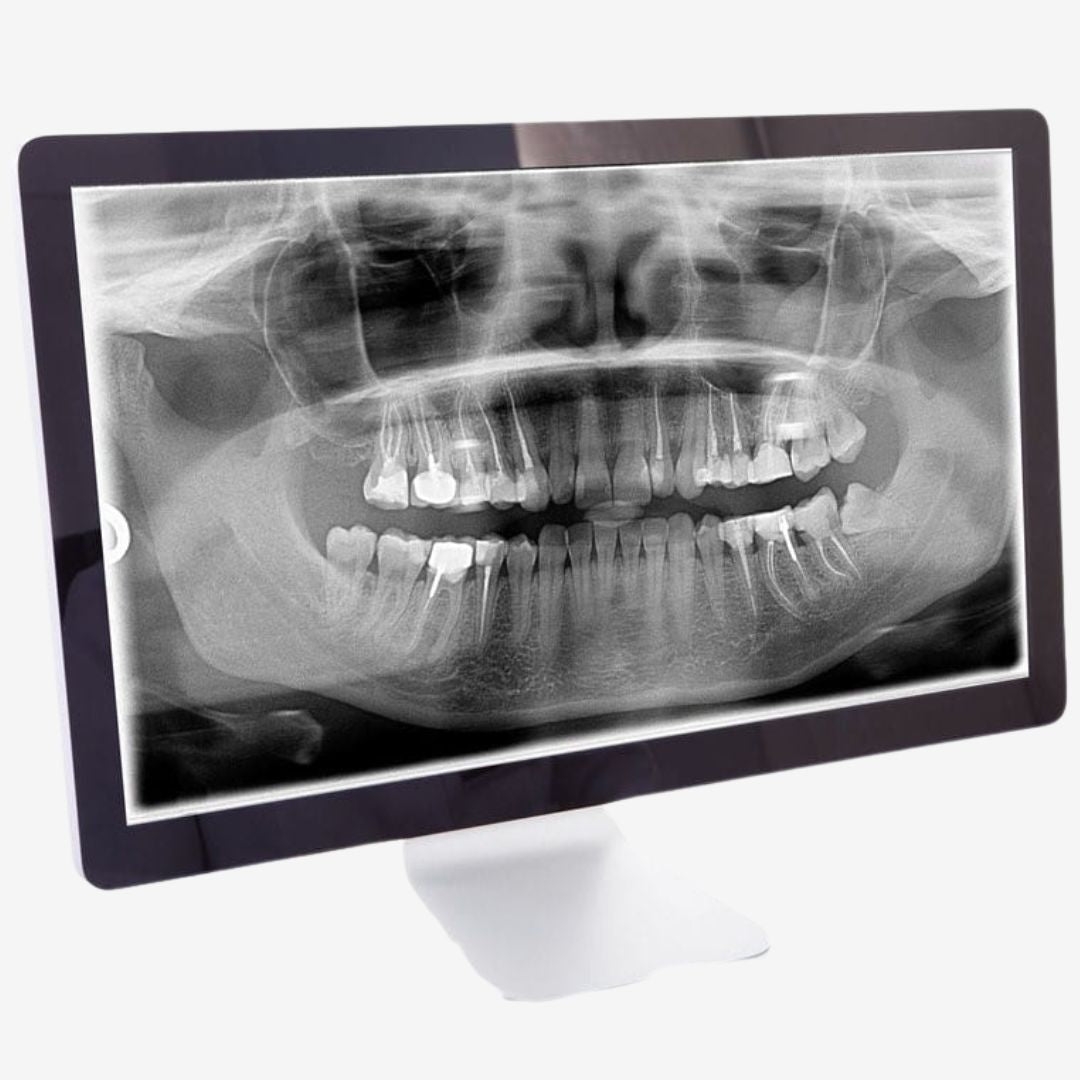

Røntgenbilder er et viktig diagnostisk verktøy i moderne tannhelse. Hos Clinica MedSpa benytter vi avansert røntgenteknologi for å få detaljerte bilder av tennene, kjeven og omkringliggende strukturer. Dette gjør det mulig for tannlegen å oppdage skjulte problemer som ikke kan sees med det blotte øye, som karies i tennene, infeksjoner under tannkjøttet, eller problemer med kjeven. Røntgenbilder gir oss en grundig innsikt i tannhelsen din, som kan bidra til tidlig påvisning av problemer og mer presis behandling.

Vi benytter digitale røntgenbilder, som gir høy oppløsning og umiddelbare resultater, samtidig som det er mer skånsomt for pasientens helse sammenlignet med tradisjonelle røntgenmetoder.

Digitale røntgenbilder er essensielt for presis diagnostikk og effektiv behandling. Vi bruker moderne røntgenteknologi som gir svært detaljerte bilder av tenner, tannrøtter, kjeveben og omliggende strukturer. Dette gjør at tannlegen raskt og nøyaktig kan identifisere problemer som karies, betennelser, infeksjoner og andre skjulte tilstander.

Digitale røntgenbilder gir tannlegen innsikt i din munnhelse som ikke er synlig ved vanlig undersøkelse. Disse bildene muliggjør tidlig diagnose, nøyaktig behandling, og forebygging av mer alvorlige problemer. Med minimal stråling og høy presisjon sikrer vi trygghet og gode resultater for din tannhelse.